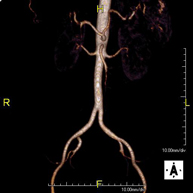

Prueba diagnóstica no invasiva que consiste en el estudio de la arteria aorta abdominal, obteniendo imágenes de alta definición anatómica mediante el empleo de un campo electromagnético y ondas de radio (con un emisor y un receptor). Es indispensable el uso de contraste paramagnético (Gadolinio). Sin embargo, no utiliza radiación ionizante. La calidad de las imágenes permite realizar reconstrucciones en 2D y 3D. Está indicado en aquellos pacientes con enfermedad vascular (aterosclerosis), estudio de aneurismas, en estudios pre-quirúrgicos de lesiones adyacentes a la aorta abdominal como "mapa" vascular, etc. - Angio RM Aorta-ilíaca

Prueba diagnóstica no invasiva que consiste en el estudio de la arteria aorta abdominal de las arterias ilíacas, obteniendo imágenes de alta definición anatómica mediante el empleo de un campo electromagnético y ondas de radio (con un emisor y un receptor). Es indispensable el uso de contraste paramagnético (Gadolinio). Sin embargo, no utiliza radiación ionizante. La calidad de las imágenes permite realizar reconstrucciones en 2D y 3D. Esta prueba está especialmente indicada como estudio pre-quirúrgico (mapa vascular) antes de intervenciones percutáneas o quirúrgicas de aorta abdominal y arterias ilíacas, estudio complementario en pacientes con isquemia de miembros inferiores, etc. - Angio RM Arterial extremidades inferiores

Prueba diagnóstica no invasiva que consiste en el estudio de la arteria aorta abdominal, obteniendo imágenes de alta definición anatómica mediante el empleo de un campo electromagnético y ondas de radio (con un emisor y un receptor). Es indispensable el uso de contraste intravenoso paramagnético (gadolinio). Sin embargo, no utiliza radiación ionizante. La calidad de las imágenes permite realizar reconstrucciones en 2D y 3D. Está indicado en aquellos pacientes con enfermedad vascular (aterosclerosis), estudio de aneurismas, en estudios pre-quirúrgicos de lesiones adyacentes a la aorta abdominal como "mapa" vascular… - Angio-RM Aorta iliaca

Prueba diagnóstica no invasiva que consiste en el estudio de la arteria aorta abdominal, obteniendo imágenes de alta definición anatómica mediante el empleo de un campo electromagnético y ondas de radio (con un emisor y un receptor). Es indispensable el uso de contraste intravenoso paramagnético (gadolinio). Sin embargo, no utiliza radiación ionizante. La calidad de las imágenes permite realizar reconstrucciones en 2D y 3D. Esta prueba está especialmente indicada como estudio pre-quirúrgico (mapa vascular) antes de intervenciones percutáneas o quirúrgicas de aorta abdominal, estudio complementario en pacientes con isquemia de miembros inferiores… - Angio-RM Arterias renales